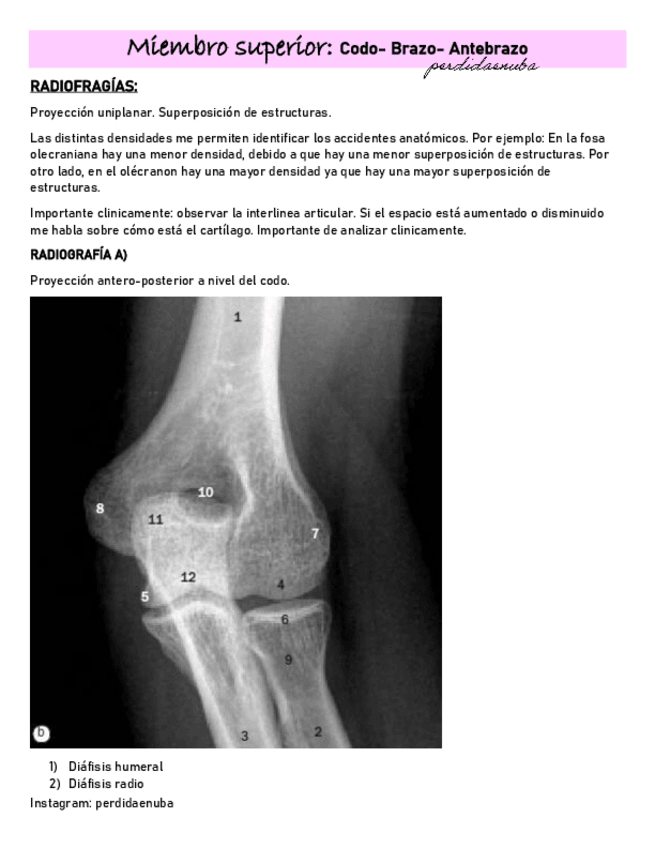

He publicado nuevos apuntes de 8º Cirugía General: BRAZO-CODO-ANTEBRAZO-.pdf

17 páginas